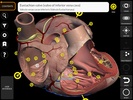

Nama Paket | com.catfishanimationstudio.MuscularSystemLite |

| Kategori | Edukasi & Bahasa | |

| Penerbit | Catfish Animation Studio | |